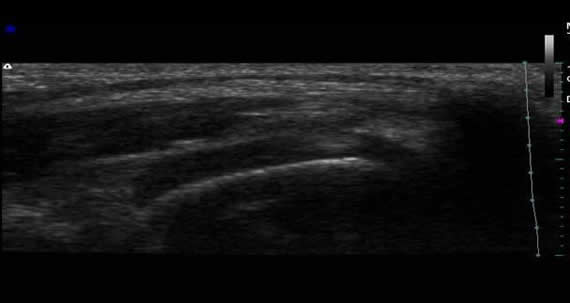

1) Ultrasonografía musculoesquelética inicial: Fotos 1 A y B. Imágenes corte longitudinal de bolsa sinovial.

(A) Se observa bursa distendida con contenido hipoecogénico (presencia de líquido). (B) Se observa con mayor detalle refuerzo acústico posterior delimitado por dos bandas hiperecoicas. En condiciones normales no suele apreciarse la bolsa sinovial.

(C) Imagen del tendón del músculo tríceps braquial, corte longitudinal con pérdida del patrón fibrilar.